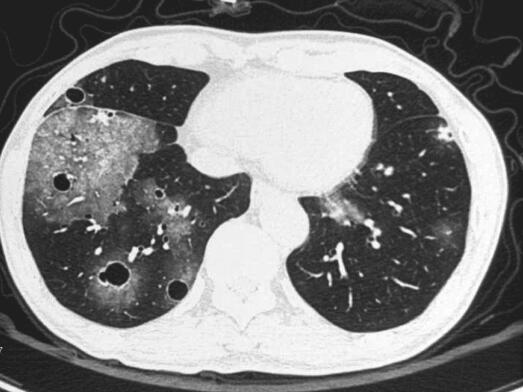

入院时生命体征平稳,体型偏瘦,余未见明显阳性体征。入院后积极完善血尿便常规、风湿免疫相关化验,如ANCA系列、补体等及痰培养、痰涂片找结核菌、痰涂片找真菌等,同时经验性给予头孢西丁联合左氧氟沙星抗感染治疗5天,患者咯血量无明显变化。期间化验回报:血细胞分析示血象正常,尿常规示潜血弱阳性,镜检红细胞数正常,ANCA、狼疮系列、补体系列均大致正常,两次痰涂片找真菌回报可见真菌孢子及菌丝,两次痰培养回报为白念珠菌,11月3日复查胸部CT(图2)示空洞病灶较前增多,空腔增大,遂调整治疗方案为头孢哌酮舒巴坦、替硝唑及卡泊芬净治疗2周,患者咯血量较前增多,约20~30ml/d,11月16日复查胸部CT(图3),双肺空腔病灶较前继续进展,11月18日行气管镜检查示左、右主支气管及其所属所见各分支支气管黏膜光滑,轻度充血水肿,各管腔内可见血性分泌物,充分吸引后可见右下基底各段支气管及左舌叶支气管管腔黏膜不断有新鲜血液溢出,以右下后基底段为主,管腔远端未见血液溢出,支气管刷检及灌洗液找结核菌均为阴性。结合患者病史、症状、体征及胸部影像学、气管镜下特点,双肺空洞病灶性质仍不明确,考虑到患者支气管管腔溢血较多,经皮肺穿刺活检出血风险大,建议其可考虑胸腔镜肺活检术,协助明确双肺病灶性质,患者本人表示拒绝。患者给予经验性抗细菌、抗真菌治疗后,双肺病灶仍有进展,提示治疗无效,停用所有抗生素,给予口服某中成药止血胶囊及更换义齿后,咯血次数逐渐减少至2~3口/日,为痰中带暗红色血块,并建议其于上级医院进一步诊治。11月26日就诊于北京某三甲医院,12月1日行胸部增强CT(图4)示双肺多发囊泡影,黏液腺癌?血管肉瘤?肺吸虫?并转入胸外科行胸腔镜下肺活检术,术中快速冰冻病理示恶性肿瘤。12月18日病理回报为肺低分化恶性肿瘤,倾向低分化癌,同时送检病理切片于外院会诊。12月26日两家医院病理会诊结果回报为低分化鳞癌。1月4日行PET-CT回报双肺内多发薄壁空洞,周围伴磨玻璃影,空洞壁代谢异常增高,右肺近肺门代谢增高结节,均考虑为恶性病变,余未见明显异常。

图3 试验性抗细菌、抗真菌治疗后胸部CT示双肺病灶继续进展